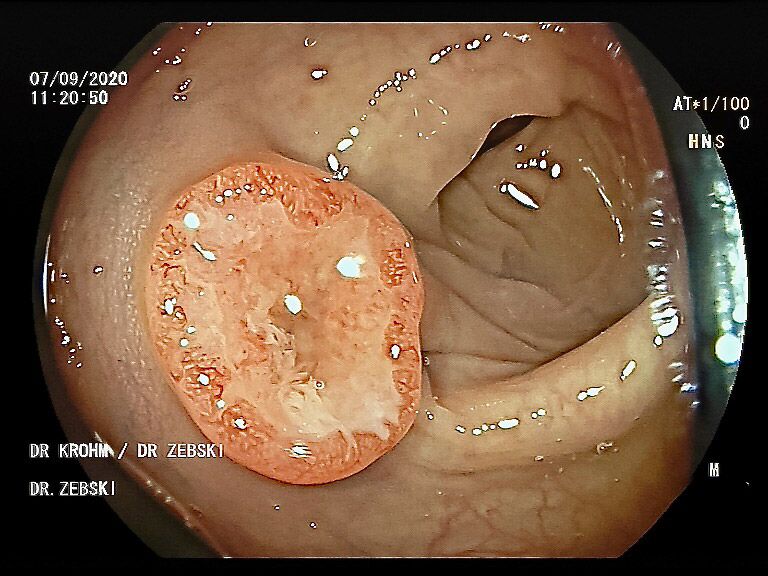

Die Darmspiegelung ist der uneingeschränkte Goldstandard für die Diagnostik und Vorsorge sämtlicher Erkrankungen des Dickdarms und des untersten Dünndarms. Die hochauflösende Bildqualität (High Definition) unserer modernen Videokoloskope ermöglicht eine zuverlässige Einordnung nahezu sämtlicher entzündlicher oder geschwulstiger Veränderungen der Dickdarmschleimhaut.

Die Darmspiegelung hilft, dass Darmkrebs gar nicht erst entstehen kann. Denn während der Untersuchung werden auch Polypen entfernt, aus denen sich der Darmkrebs in der Regel entwickelt. Von allen Maßnahmen zur Früherkennung dieser Polypen besitzt die Koloskopie die höchste Empfindlichkeit. Sie weist kleinste Polypen, aber auch Darmkrebs nach, der noch keinerlei Symptome macht. Die Abtragung dieser Polypen erfolgt direkt, wenn sie entdeckt werden. Das geschieht völlig schmerzfrei. Durch die Abtragung der Polypen kann die Entstehung von Darmkrebs effektiv verhindert und die krebsbedingte Sterblichkeit gesenkt werden.